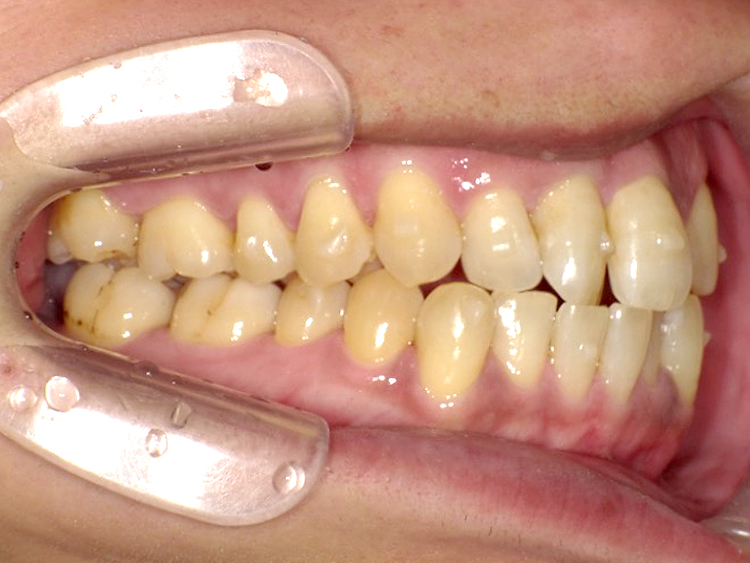

症例4

Before

After

| 主訴 | 上下前歯のがたつき |

|---|---|

| 年齢 | --- |

| 治療 期間 |

約9ヶ月 |

| 治療 内容 |

インビザラインiGoで上下顎の治療。 |

| 治療費 | ¥550,000(税込)/調整料含む |

| 治療のリスク | 矯正終了後は、リテーナーを指示通りに使用し、歯の後戻りを防ぐ必要があります。 |